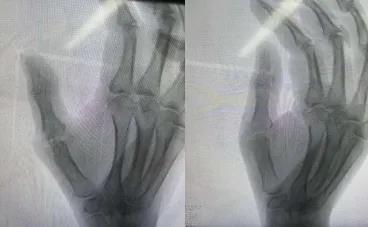

董玉金主任详细询问了李大姐的病情发展过程,并进行了全面细致的查体及拍摄X片后诊断为“右手第一掌指关节炎伴关节脱位”并建议手术治疗。

在科室病例讨论会上,董玉金主任指出:“患者大约2年前扭伤右手拇指,当时出现右手第一掌指关节处疼痛,考虑是扭伤了掌指关节韧带并出现关节囊撕裂,也未进行有效固定或治疗,掌指关节长期处于一个半脱位和长期慢性磨损的状态,并最终发展为骨性关节炎,疼痛难忍,严重影响正常活动。董玉金主任建议目前有两种手术方案,一是行掌指关节融合术;二是行掌指关节假体置换术。